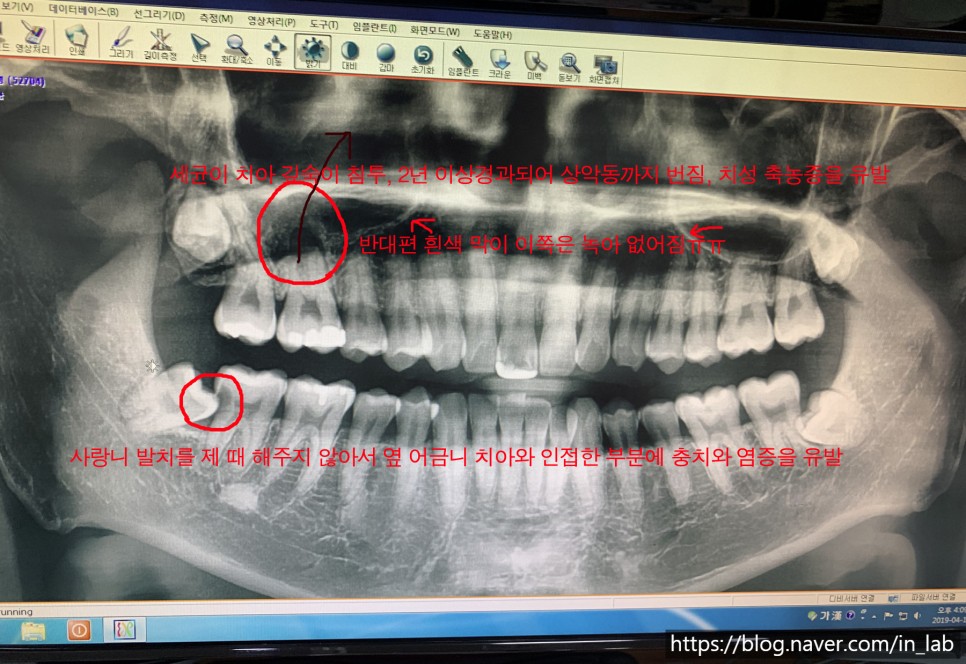

위에 사진에 빨간색 동그라미 보자 치아 엑스레이는 항상 좌우가 다르게 찍힌다고 생각해 주시기 바랍니다.

나의 경우 26번 치아는 충치가 심해서 그 전에 충치로 악화되었는데 그때 너무 가난해서 충치 치료를 했고 충전재를 가장 싼 아말감을 사용해 치료를 했다.

아말감 자체가 나쁜 소재는 결코 아니다.내구성이 약했기 때문에 이것이 망가져 덩어리째 빠져 나갈 뿐이었다. 이것을 모르고 음식을 삼키면 체내에서 수은 중독과 같은 문제를 일으킬 수 있다.

중요하지 않다고 생각해 그 후에도 생활을 계속했지만 갈라진 틈으로 충치균이 계속 치아를 망가뜨렸다.

치아만 망가뜨린 것이 아니라 신경관을 타고 치아의 신경관 뿌리까지 내려가 잇몸 깊숙이 염증을 일으켰을 뿐만 아니라

23년 경과하자 26번 어금니와 콧속의 상악동이라는 공간을 구분하는 세포막을 녹여 버린 것이다.

이처럼 사진상의 화살표 방향과 같이 세균이 상악동까지 침투하여 축농증을 유발하고 이것이 의학적 용어로 ‘치성축농증’이라 불리는 치과성 비염, 축농증 형태의 질환이다.